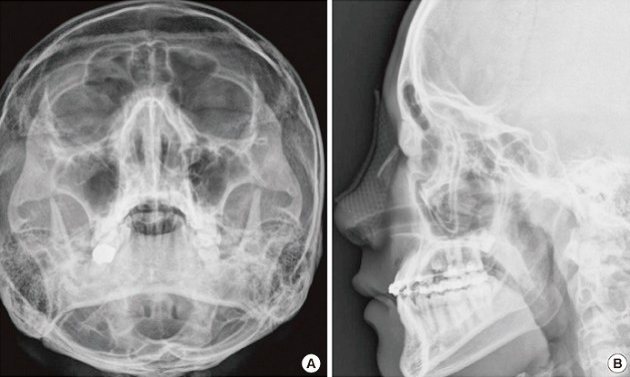

В настоящее время наиболее информативными являются инструментальные методы диагностики перелома носа. Например, такие как:

- рентгенография;

- компьютерная томография;

- эндоскопический осмотр.

При помощи рентгенографии врач определяет линию перелома, оценивает смещение костных носовых отломков, определяет наличие отломков носа в мягких тканях.

Компьютерная томография дает более точную информацию и линиях перелома носа, возможном смещении костных носовых отломков.

При этом можно выявить повреждения глазниц, носовых пазух и костей черепа.